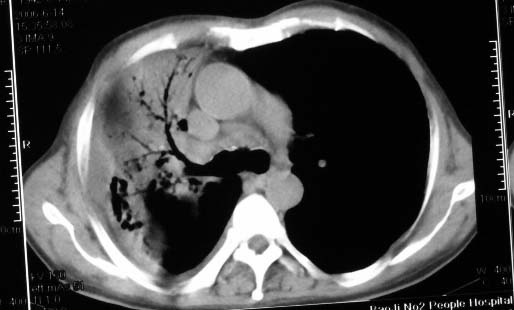

抗炎10天后无好转出现胸水,考虑:肺结核合并间质纤维化

抗感染病变无明显改善,右上叶大片状增弥不均匀病灶,夹杂网状及支气管充气像,肺门纵隔淋巴结肿大,右侧胸腔积液。考虑1混合感染伴肺间质改变[警惕特殊感染,如真菌]。2细支气管肺泡癌。建议结合临床及进一步检查[如痰,胸水脱落细胞检查及支气管镜检灌洗或穿刺活检

影象表现:右肺上叶大片状、网格状及索条致密影,蜂窝影,其内参杂斑点状小结节,密度不均匀,内见枯枝样含气支气管像,纵隔内见肿大淋巴结.胸膜广泛增厚,前胸壁似受累.少量胸腔积液.纵隔内淋巴结的直径>1.5cm.右侧胸廓体积缩小.考虑:1 肺结核合并间质纤维化 2 细支气管肺泡癌

右肺上叶大片状、网格状及索条致密影,蜂窝影,其内参杂斑点状小结节,密度不均匀,内见枯枝样含气支气管像,纵隔内见肿大淋巴结.胸膜广泛增厚,前胸壁受累增厚.少量胸腔积液.纵隔内淋巴结的直径>1.5cm.右侧胸廓体积缩小.考虑: 细支气管肺泡癌并肺内癌性淋巴管炎。